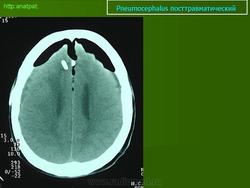

A) NEUMOCÉFALO POSTRAUMÁTICO: Es una complicación muy grave de un traumatismo craneoencefálico y se produce por fractura de la pared de los senos paranasales o de la base del cráneo. Cuando una persona sufre un accidente muy violento, como sucede en los de tráfico, se producen múltiples fracturas de cráneo. Si alguna rompe la pared de los senos paranasales y una esquirla ósea desgarra la duramadre, el aire penetra al interior del cráneo y se acumula en cualquiera de los espacios intracraneales, aunque fundamentalmenteen el subaracnoideo. En el topograma preliminar de una TC se aprecia una imagen hipodensa que representa el gas depositado en el espacio subaracnoideo frontal (flechas) porque al realizar la exploración en decúbito supino el aire asciende hacia las partes más elevadas de la cavidad craneal. (Figura 1).

FIGURA 1) Neumocéfalo postraumático. El aire, que ha penetrado en el espacio subaracnoideo de las cisternas basales como consecuencia de la fractura del techo del seno esfenoidal y de la duramadre, asciende por gravedad al espacio subaracnoideo frontal, donde forma un nivel (flechas)